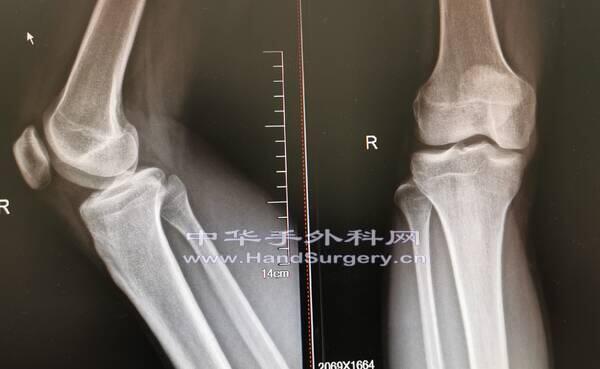

今天上午门诊,一个21岁大学生来测骨龄

看看还能不能长个儿

现在168cm

拍照腕关节正侧位和膝关节正侧位片

你们看看他还能再窜一窜吗